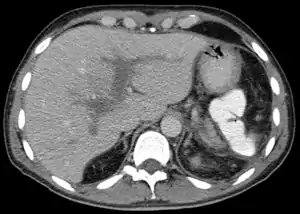

| ترومبوز وریدپورت در نمای سیتی اسکن | |

تشخیص این عارضه معمولاً توسط سونوگرافی، سیتی اسکن با کنتراست و یا امآرای صورت میگیرد. همچنین آزمایش سطح خونی دیدایمر نیز میتواند در تشخیص این بیماری کم کننده باشد، زیرا در ترومبوز وریدپورت میزان شکستن فیبرین افزایش یابد و این اتفاق منجر به افزایش سطح دیدایمر خواهد شد.